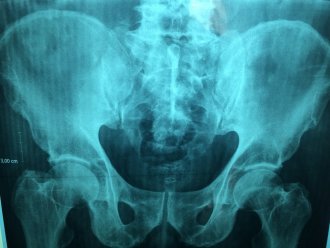

Snimak pokazuju da je telo pacijenta koji je tražio pomoć zbog upornog kašlja puno larvi pantljičare.

Rendgenski snimak stomaka, koji je objavio brazilski lekar, pokazuje stotine svetlih tačaka, od kojih svaka predstavlja kalcifikovane ostatke parazita. Ovo stanje, nazvano cisticerkoza, nastaje kada larve neke vrste pantljičare, koja inače živi u crevima, uđu u tkiva poput mišića ili mozga. Tamo formiraju čvrste čvorove poput cista koje se mogu osetiti kao kvržice ispod kože.

Dr De Souza kaže da se cisticerkoza dobija gutanjem jaja pantljičare, prisutne u izmetu ljudi zaraženih ovim parazitom.

Dodao je da u većini ovakvih slučajeva pacijentu nije potrebno nikakvo lečenje.

- Ako nemate nikakvu povredu unutar glave, kičmene moždine ili očiju, ne morate čak ni da lečite - rekao je brazilski lekar pojašnjavajući da su lezije kalcifikovane tako da larve u njima ne mogu da prežive.

- Ako to ne izaziva nikakvu nelagodu, život se nastavlja - kazao je.

On je, međutim, potvrdio da je pacijent čekao magnetnu rezonancu kako bi proverio lokaciju cisti jer ako su locirane u mozgu mogu biti i smrtonosne. Obično je u ovim slučajevima potrebna operacija za uklanjanje cista.

Ciste takođe mogu doći do očiju gde mogu izazvati zamagljen ili poremećen vid i potencijalno izazvati infekciju. Same ciste se mogu razviti tek mesecima ili godinama nakon početne infekcije jajima pantljičare.